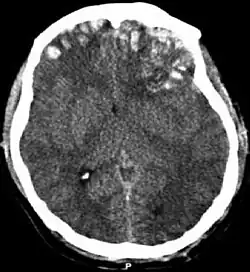

Cerebral kontusion eller hjernekontusion (latin: contusio cerebri), en form for traumatisk hjerneskade, er blå mærker på hjernevævet.[1] Ligesom med blå mærker i andet væv, kan cerebrale kontusioner associerers med flere mikroblødninger, små blodkar der lækker ind i hjernevævet. Kontusioner sker i 20-30 % af de svære hovedskader.[2] En cerebral laceration er en lignende skade, bortset fra, ifølge deres respektive definitioner, pia-arachnoid-membranerne er revet over på skadesstedet ved en laceration, og ikke er revet over ved en kontusion.[3][4] Skaden kan skabe en forringelse i mental funktion over tid, og i den akutte fase kan den resultere i hjernekompression, en livfarlig tilstand i hvilken dele af hjernen presses forbi dele af kraniet.[2] Derfor er formålet med behandling at forhindre farlige stigninger i intrakranialt tryk, trykket inde i kraniet.